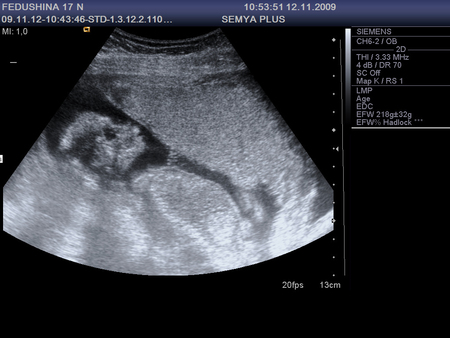

18 неделек

Результаты: УЗИ, КТГ, доплера, скринингаулыбается))) а вот он или она - не показался, хитрюга)